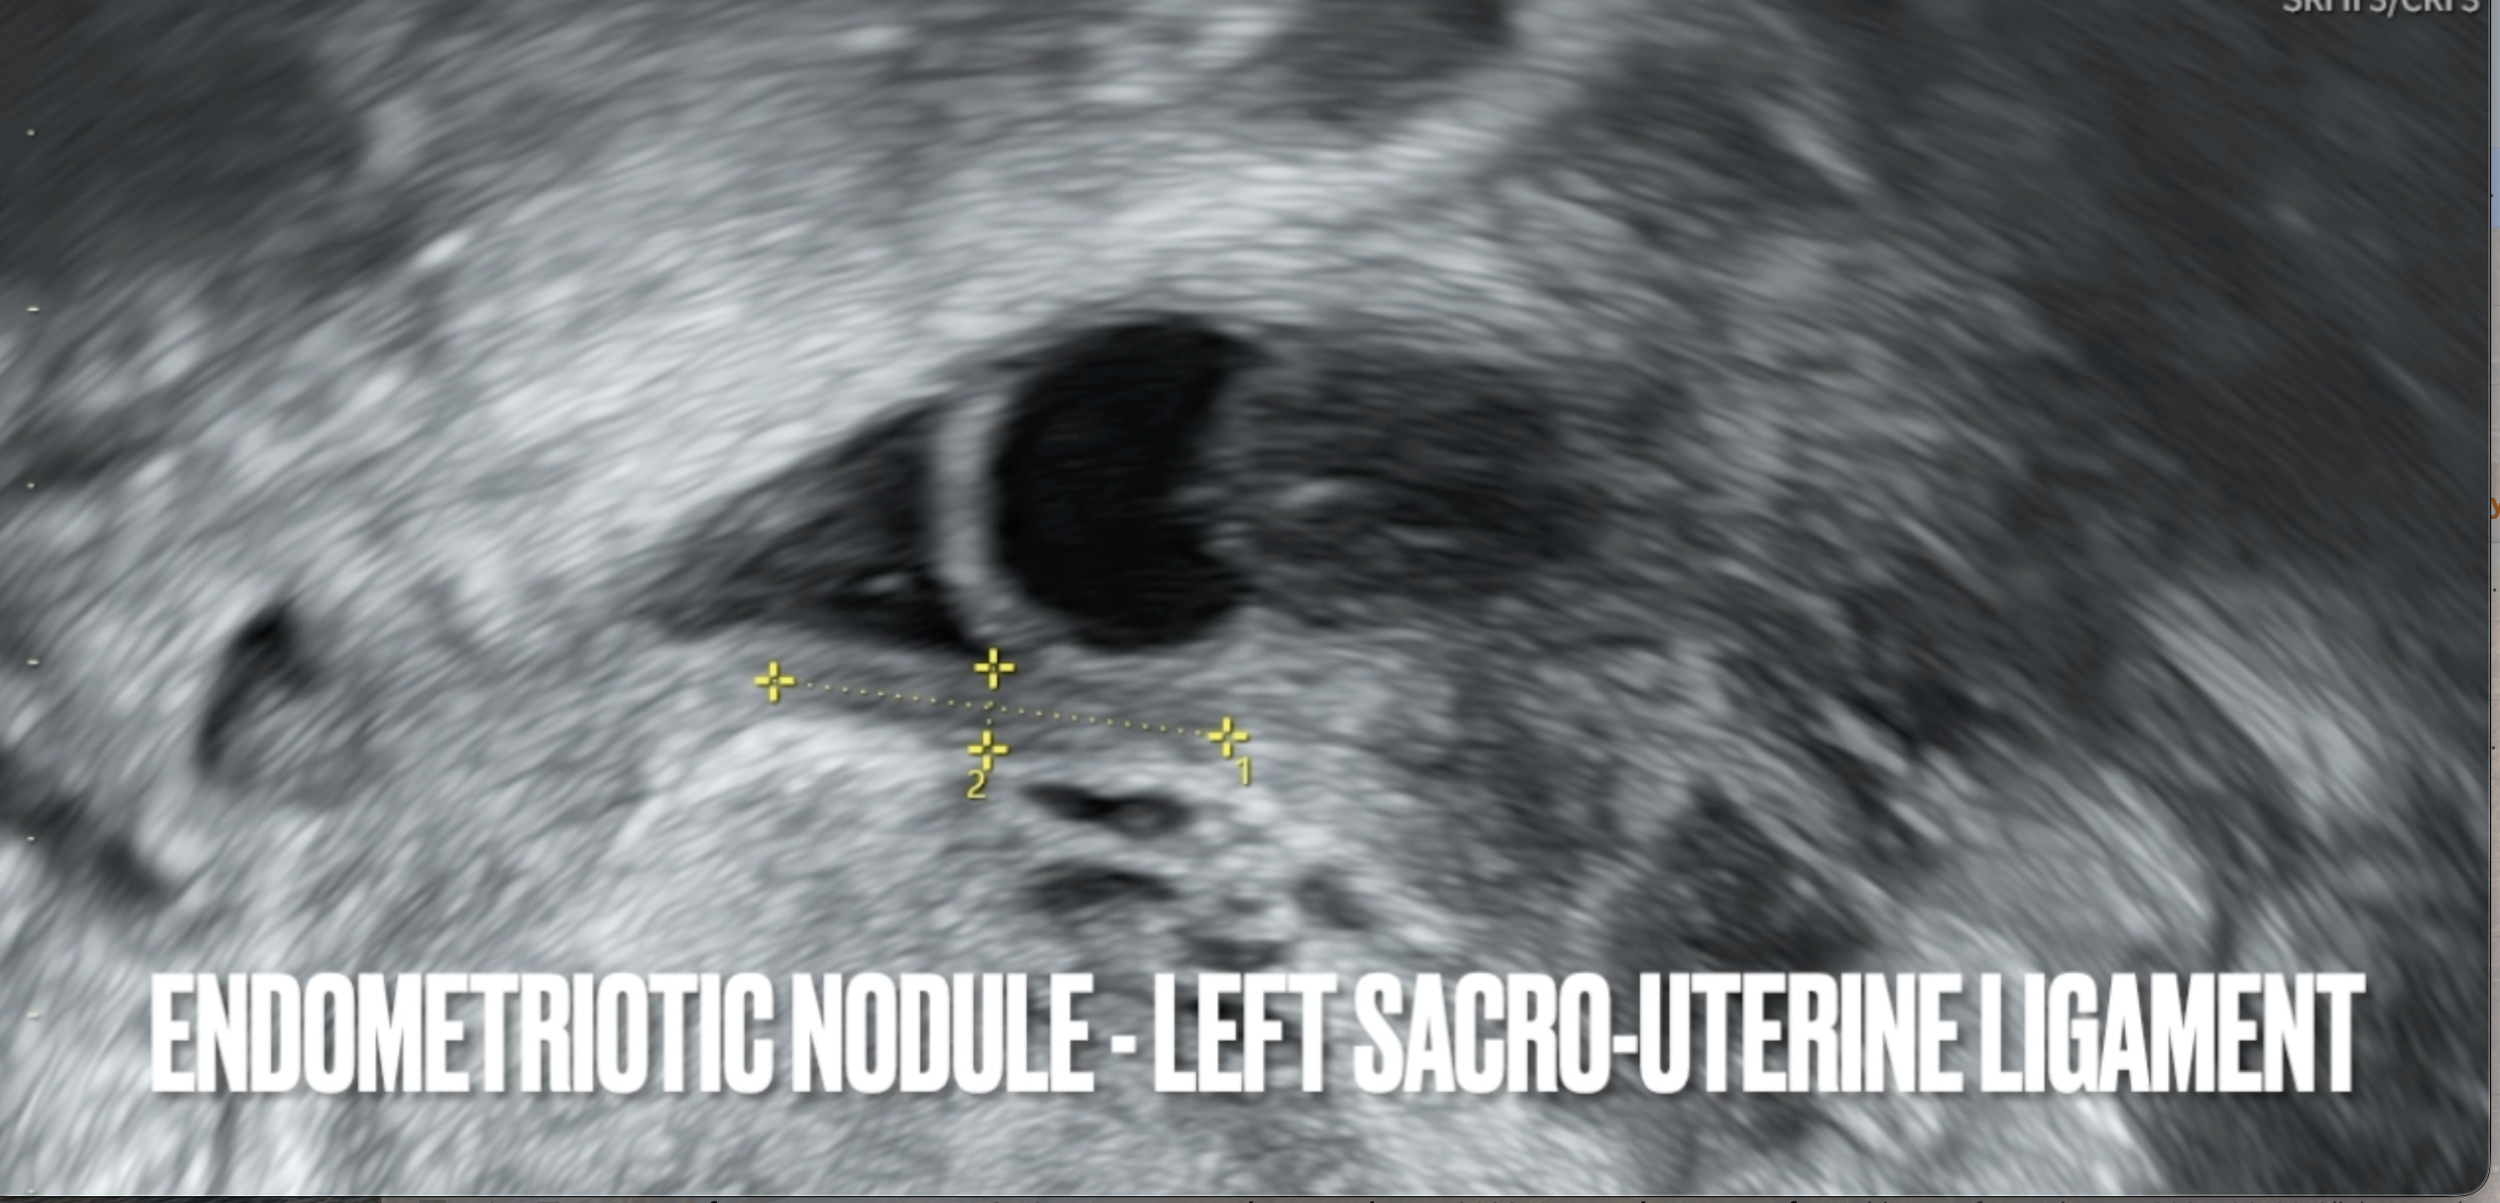

Here is a screenshot demonstrating how you can see, measure, and diagnose deep infiltrating endometriosis on ultrasound.

Thanks to them, I now have an objective way of seeing if the lesions are worsening/improving.